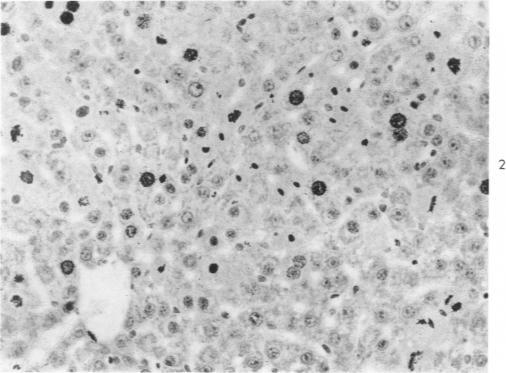

Regeneration of the liver. Absence of a "humoral factor" affecting hepatic regeneration in parabiotic rats.

Am J Pathol. 1961 Nov;39(5):561-78.